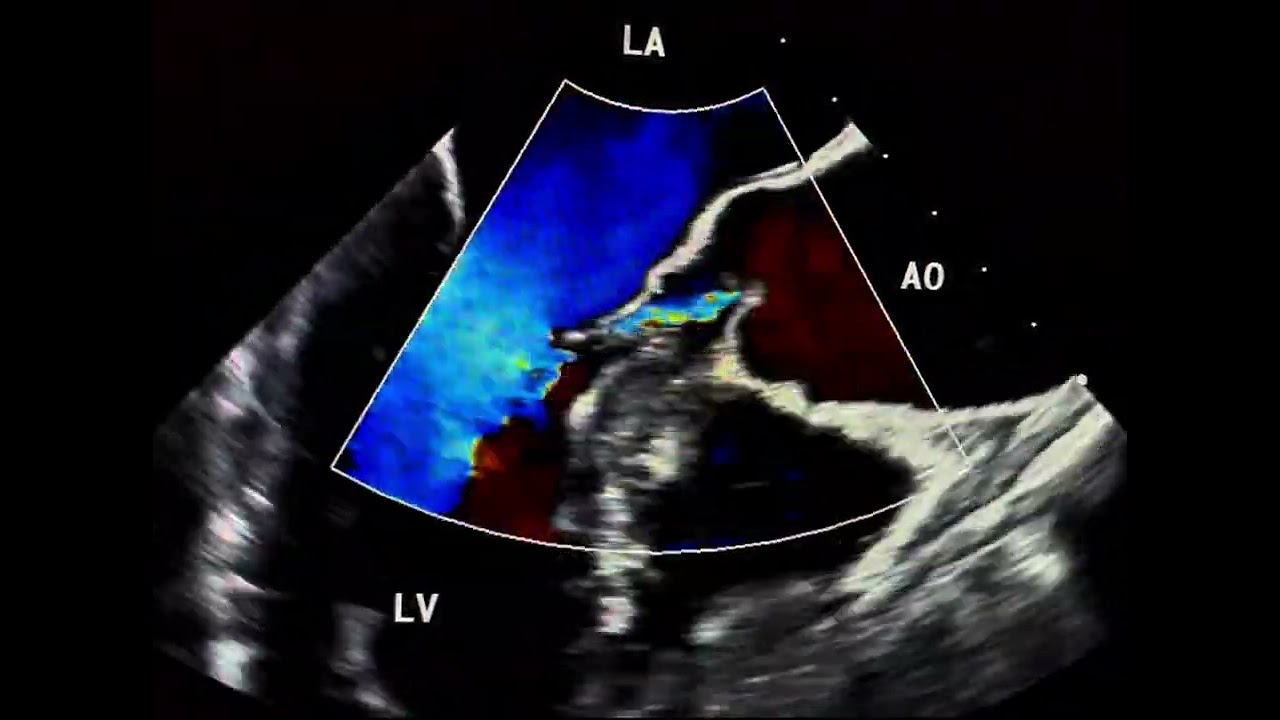

A spherical left ventricle represents pathologic remodeling, where ventricular geometry shifts from its normal ellipsoid form to a more spherical shape. increasing sphericity predicts heart failure hospitalization and sudden cardiac death, independent of ejection fraction.

The sphericity index is calculated as the ratio of short-axis diameter to long-axis length in the apical four-chamber view. Normal values are around 0.5 to 0.6; values above 0.7 are pathologic.